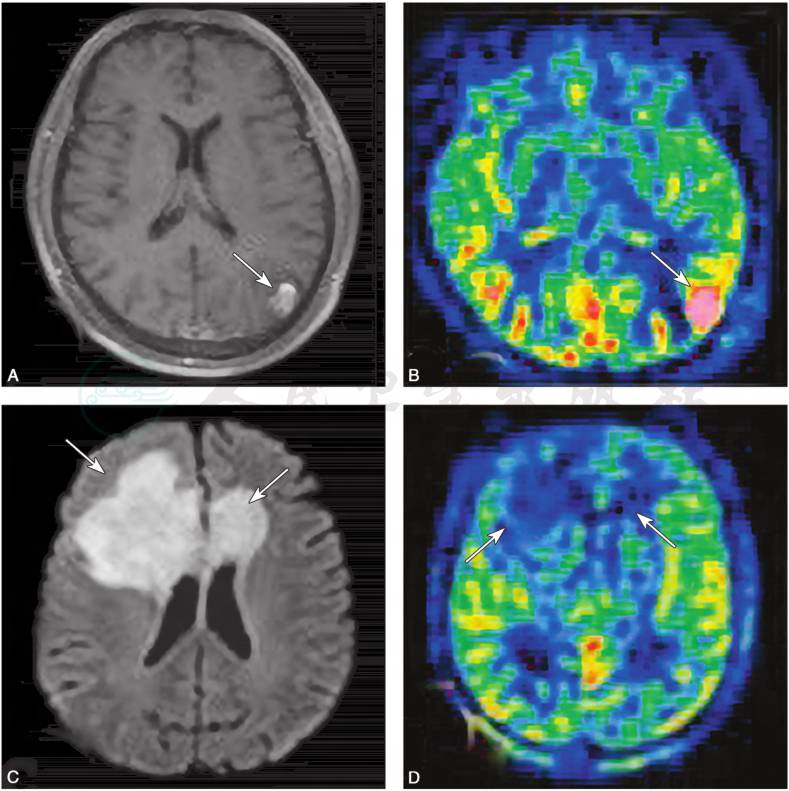

4)灌注加权成像(perfusion weighted imaging,PWI):

可用来评价病灶内的血流灌注情况,主要有两种方法:①需静脉团注外源性对比剂(如Gd-DTPA)的动态磁敏感对比增强(dynamic susceptibility contrast-enhanced,DSC)方法;②完全无创的动脉自旋标记(arterial spin labeling,ASL)方法。胶质瘤新生血管多,往往呈高灌注,而TIDD一般不出现高灌注表现(图8)。

图8灌注加权成像

病例1,女性,50岁,主因“癫痫1天”入院,胶质母细胞瘤,轴位T1WI增强示:左侧顶枕交界皮质可见结节样强化病灶(A),在 ASL像呈高灌注(B);病例2,男性,44岁,主因“意识障碍3天”入院,急性起病,TIDD,轴位DWI(C)示:双侧额叶皮质下及侧脑室旁白质可见大片融合蝶形病灶,累及胼胝体膝部,ASL显示双侧病灶处灌注无明显增高(D)

引自:神经病学:全2册.第3版.ISBN:978-7-117-31406-0.主编: